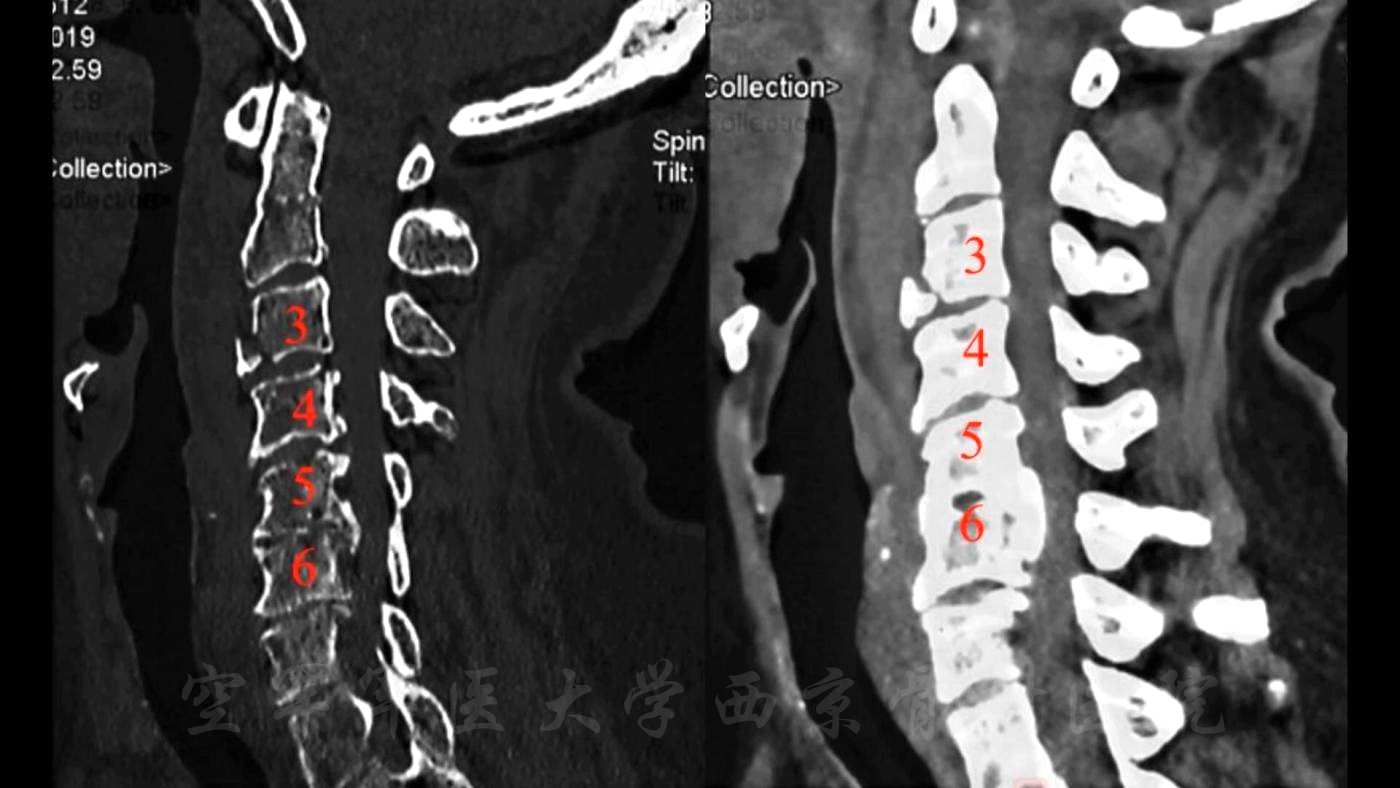

术前X线正侧位片

术前CT